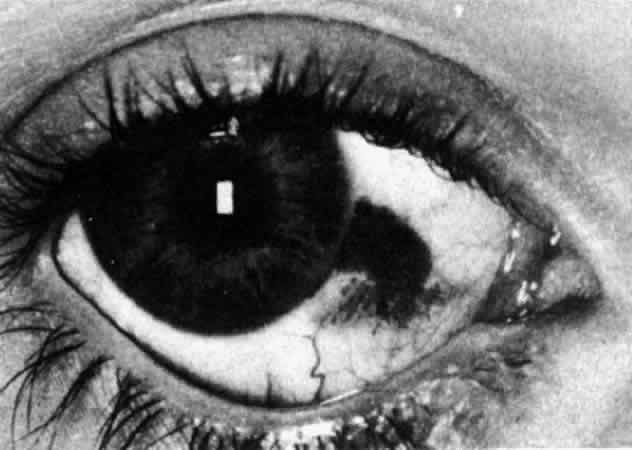

Fig. 41. Late stage of fluorescein angiogram adjacent to the site of necrosis in

the same patient as in Figure 40. Although the eye is uniformly congested, the area near the necrosis shows

vascular shutdown, whereas the rest of the conjunctiva and episclera

is normally perfused. Fig. 41. Late stage of fluorescein angiogram adjacent to the site of necrosis in

the same patient as in Figure 40. Although the eye is uniformly congested, the area near the necrosis shows

vascular shutdown, whereas the rest of the conjunctiva and episclera

is normally perfused.

|